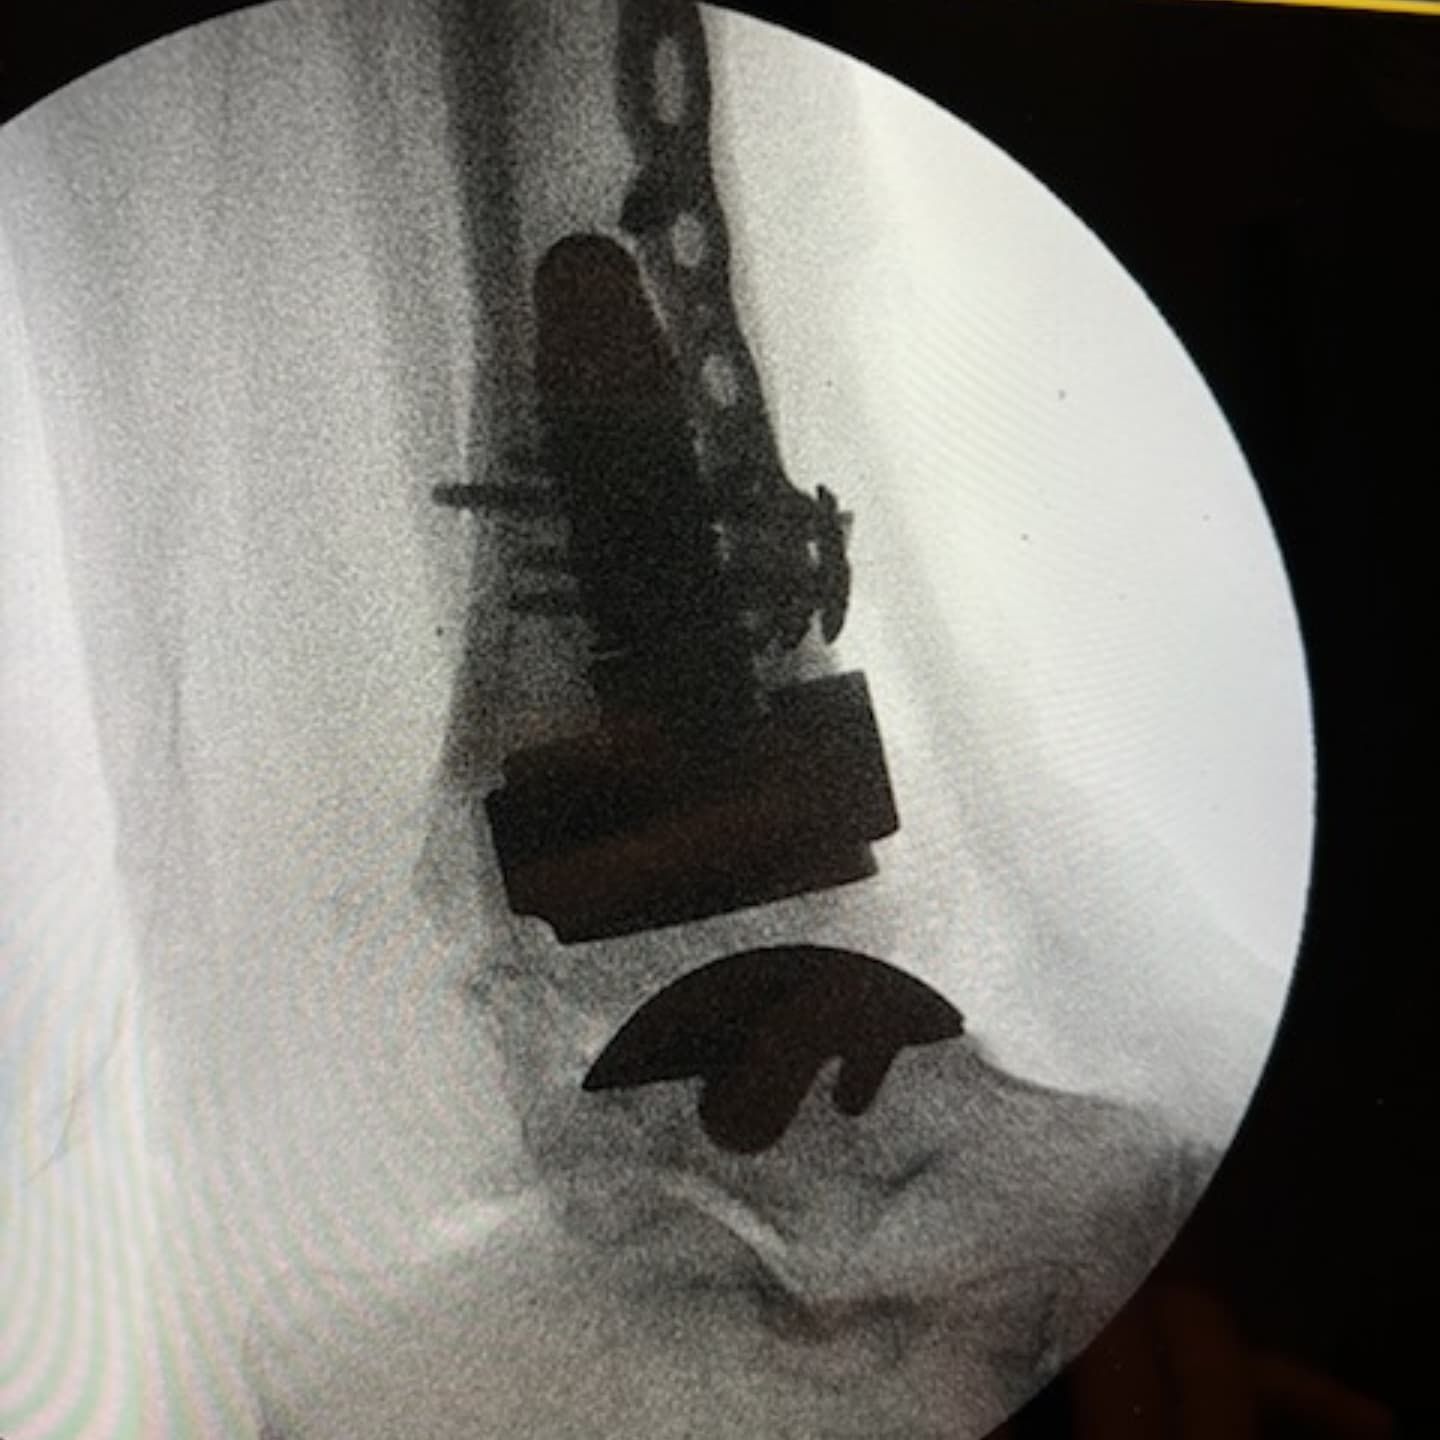

It has been a busy couple of months, but it was a pleasure to fly to Perth to help my friend and colleague Dr Unsworth-Smith with his revision ankle replacement and also to have Dr Ali Vakili observe our technique for ankle replacements.

SPECIAL GUESTS - A DAY IN THEATRE FOR MY NON-SURGICAL SUPPORT TEAM Was great to have "special guests", my own long suffering, hard working secretary @lizzie_hunter01 and podiatrist Helen from @inspire__podiatry who has helped me with my countless post op and foot and ankle patients all these years. They came to theatre to get a glimpse of how surgeries/operating theatres function, so hopefully they can understand, empathise and work better with our patients pre and post op. Helen just wanted to see a total ankle replacement 🤪.